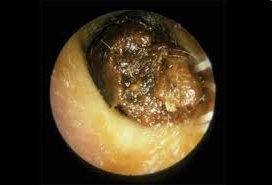

Cerumen

Waxy substance